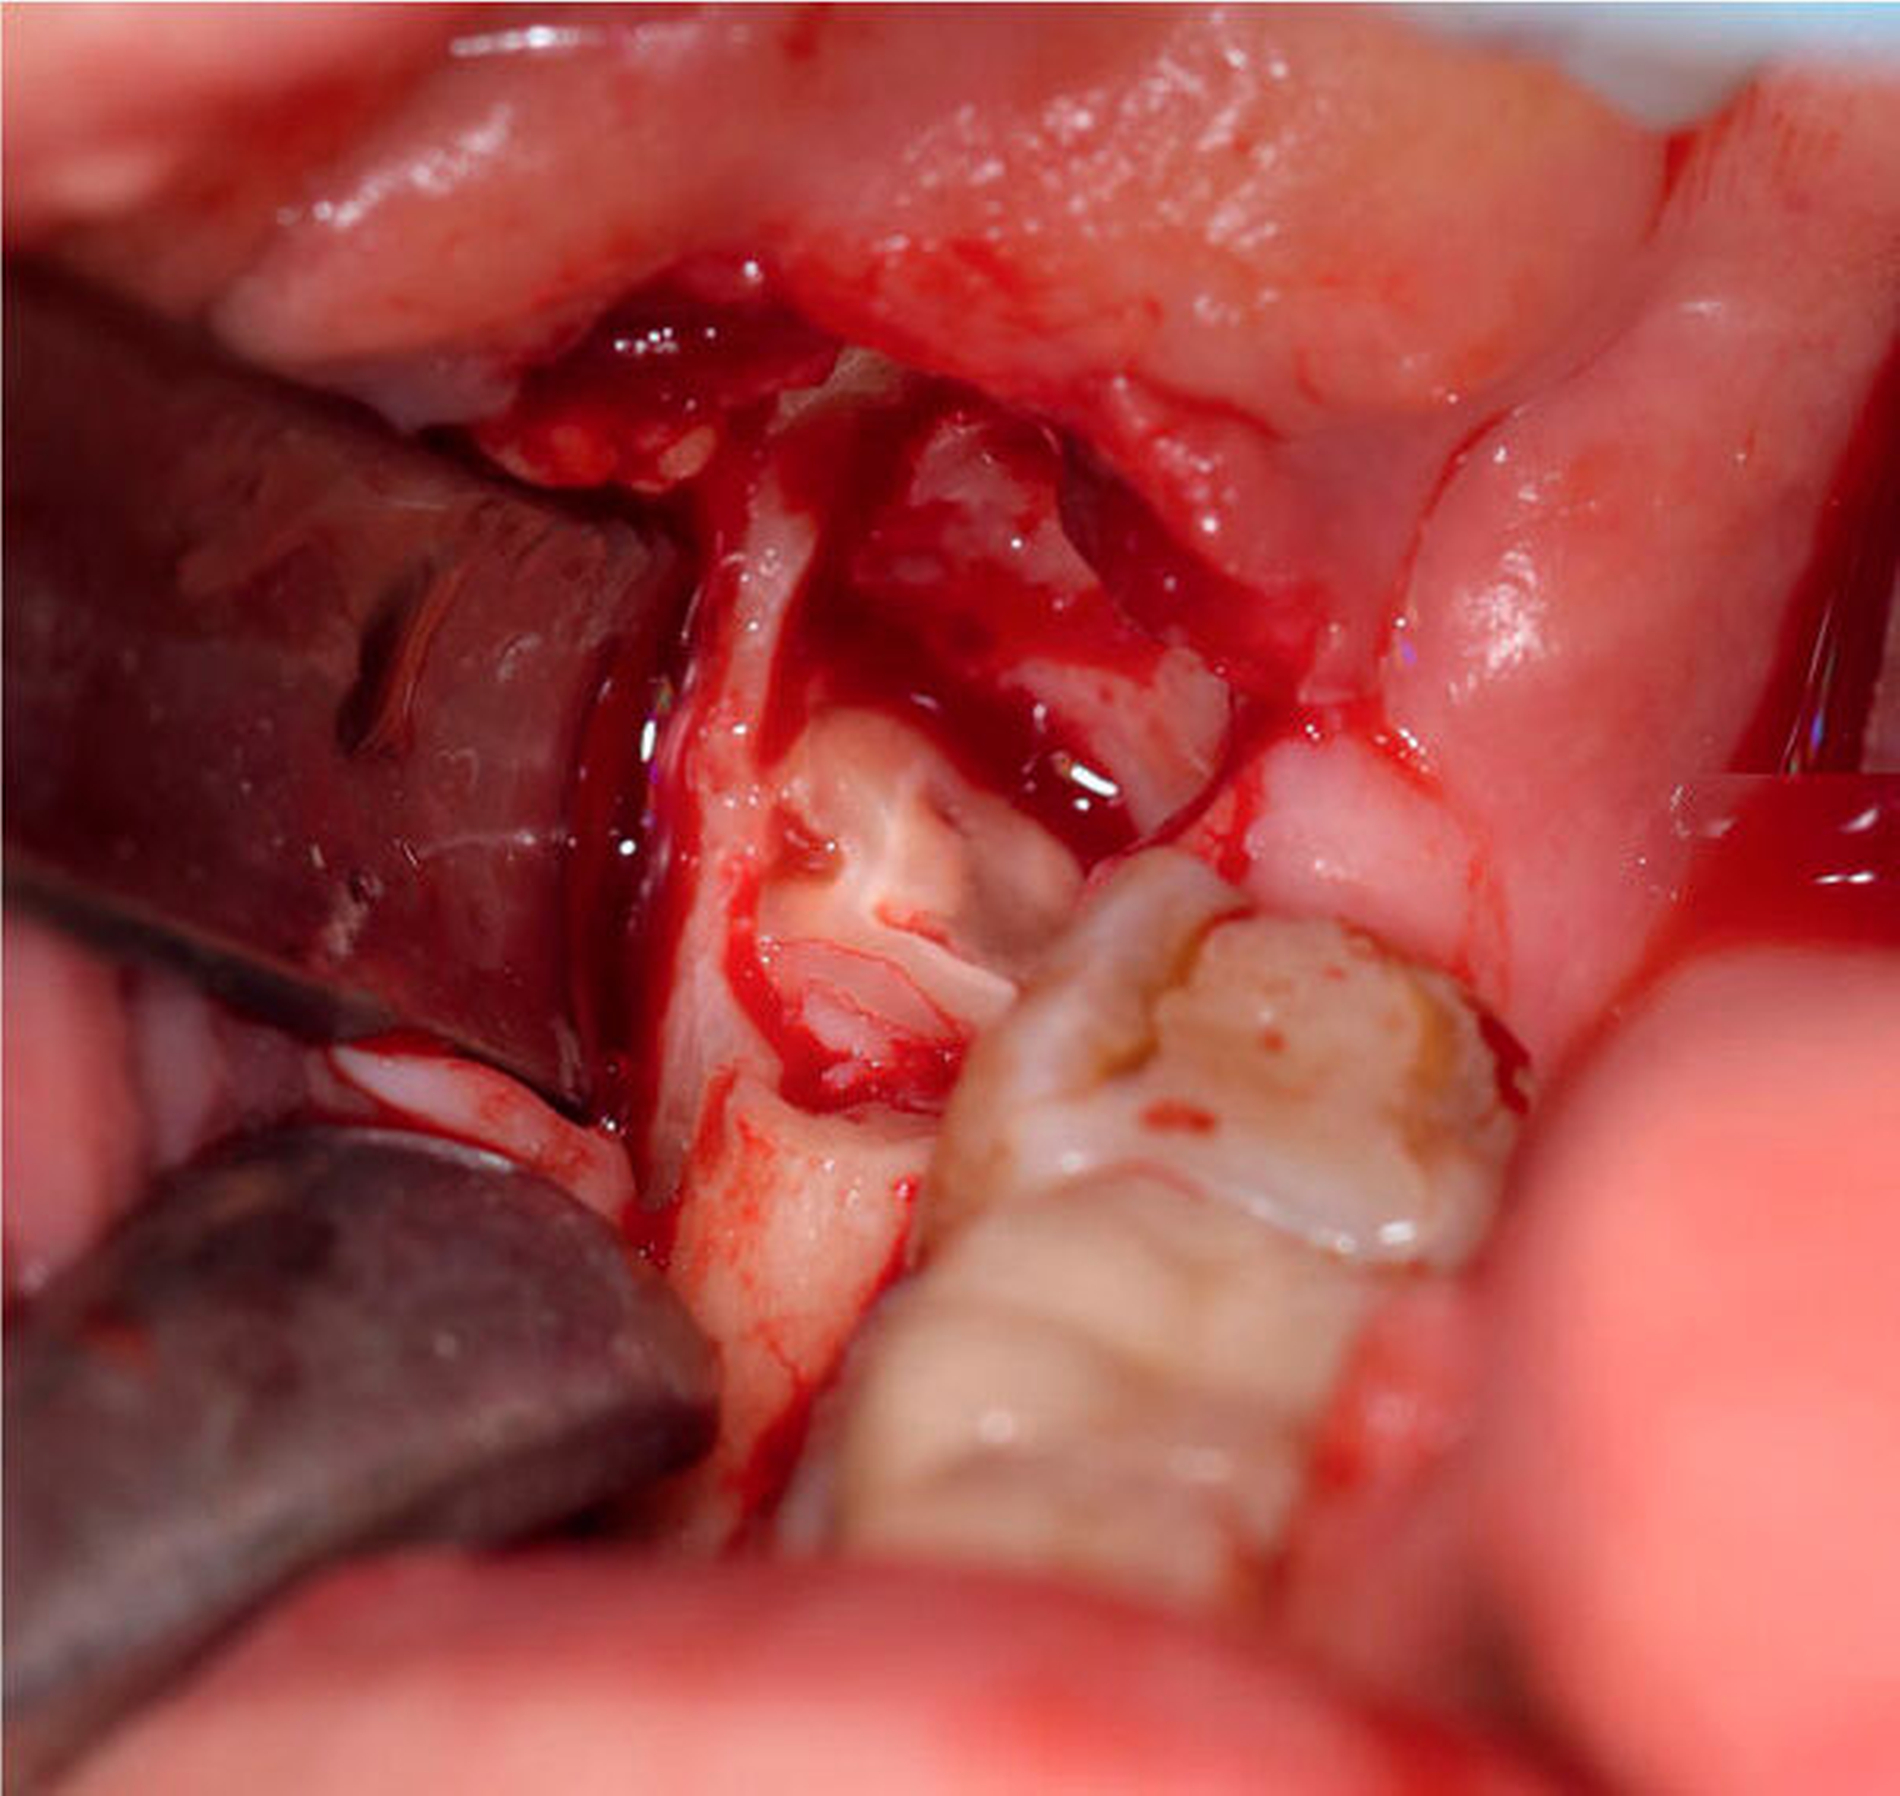

Wir entschieden uns zunächst für die klassische operative Entfernung der Zähne 28 und 38. Aufgrund des Risikos einer Nervschädigung bei der Entfernung des Zahnes 48 wurde zudem eine Koronektomie des Zahns in ambulanter Intubationsnarkose beschlossen. In Regio 48 wurde nach Schnittführung von retromolar nach distal 47 mit vestibulärer Entlastung und Bildung eines Mukoperiostlappens der Zahn 48 freigelegt (Abbildung 4). Die Zahnkrone konnte komplikationslos abgetrennt werden, woraufhin die Glättung des Wurzelblocks bei guter Sicht möglich war (Abbildung 5). Dabei wurde streng darauf geachtet, alle Schmelzanteile resektiv zu entfernen. Anschließend wurden die Wundflächen gereinigt und die Wunde durch Nähte verschlossen. Der postoperative Verlauf war unauffällig und die Patientin wurde am gleichen Tag in die ambulante Nachsorge entlassen. Zur Entzündungsprophylaxe erhielt sie Schmerzmittel. Des Weiteren wurde ihr geraten, eine starke Kaubelastung zu vermeiden.